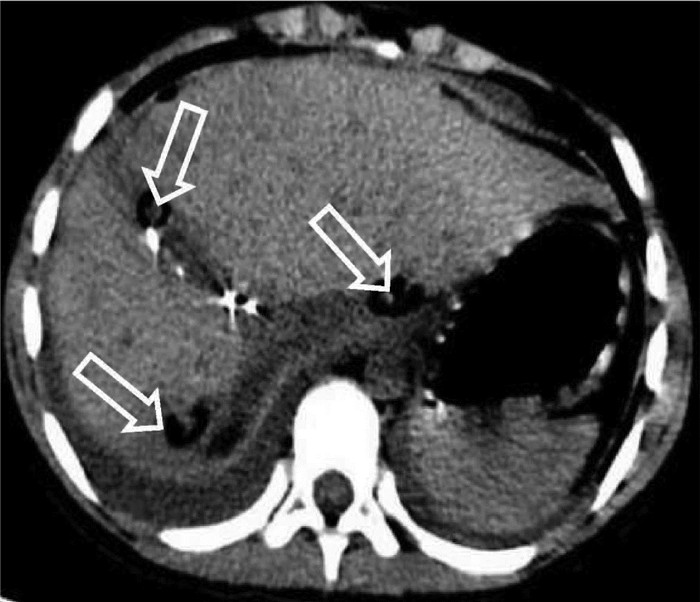

肝脏遗传性出血性毛细血管扩张症1例报告

王婷婷, 马亮, 陈建平

2022, 38(2): 423-425. DOI: 10.3969/j.issn.1001-5256.2022.02.032

摘要(1110) HTML (367) PDF (2696KB)(54)

摘要: